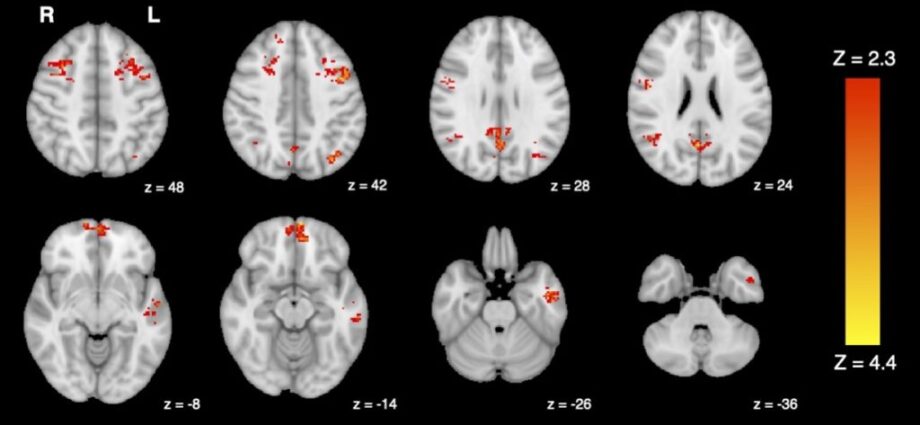

O primeiro estudo do mundo sugere que mesmo uma breve exposição à poluição do ar tem impactos rápidos no cérebro. Por Universidade da Colúmbia Britânica com informações de Science Daily Um novo estudo mostrou que níveis comuns de poluição no trânsito podem prejudicar a função do cérebro humano em apenasContinue Reading